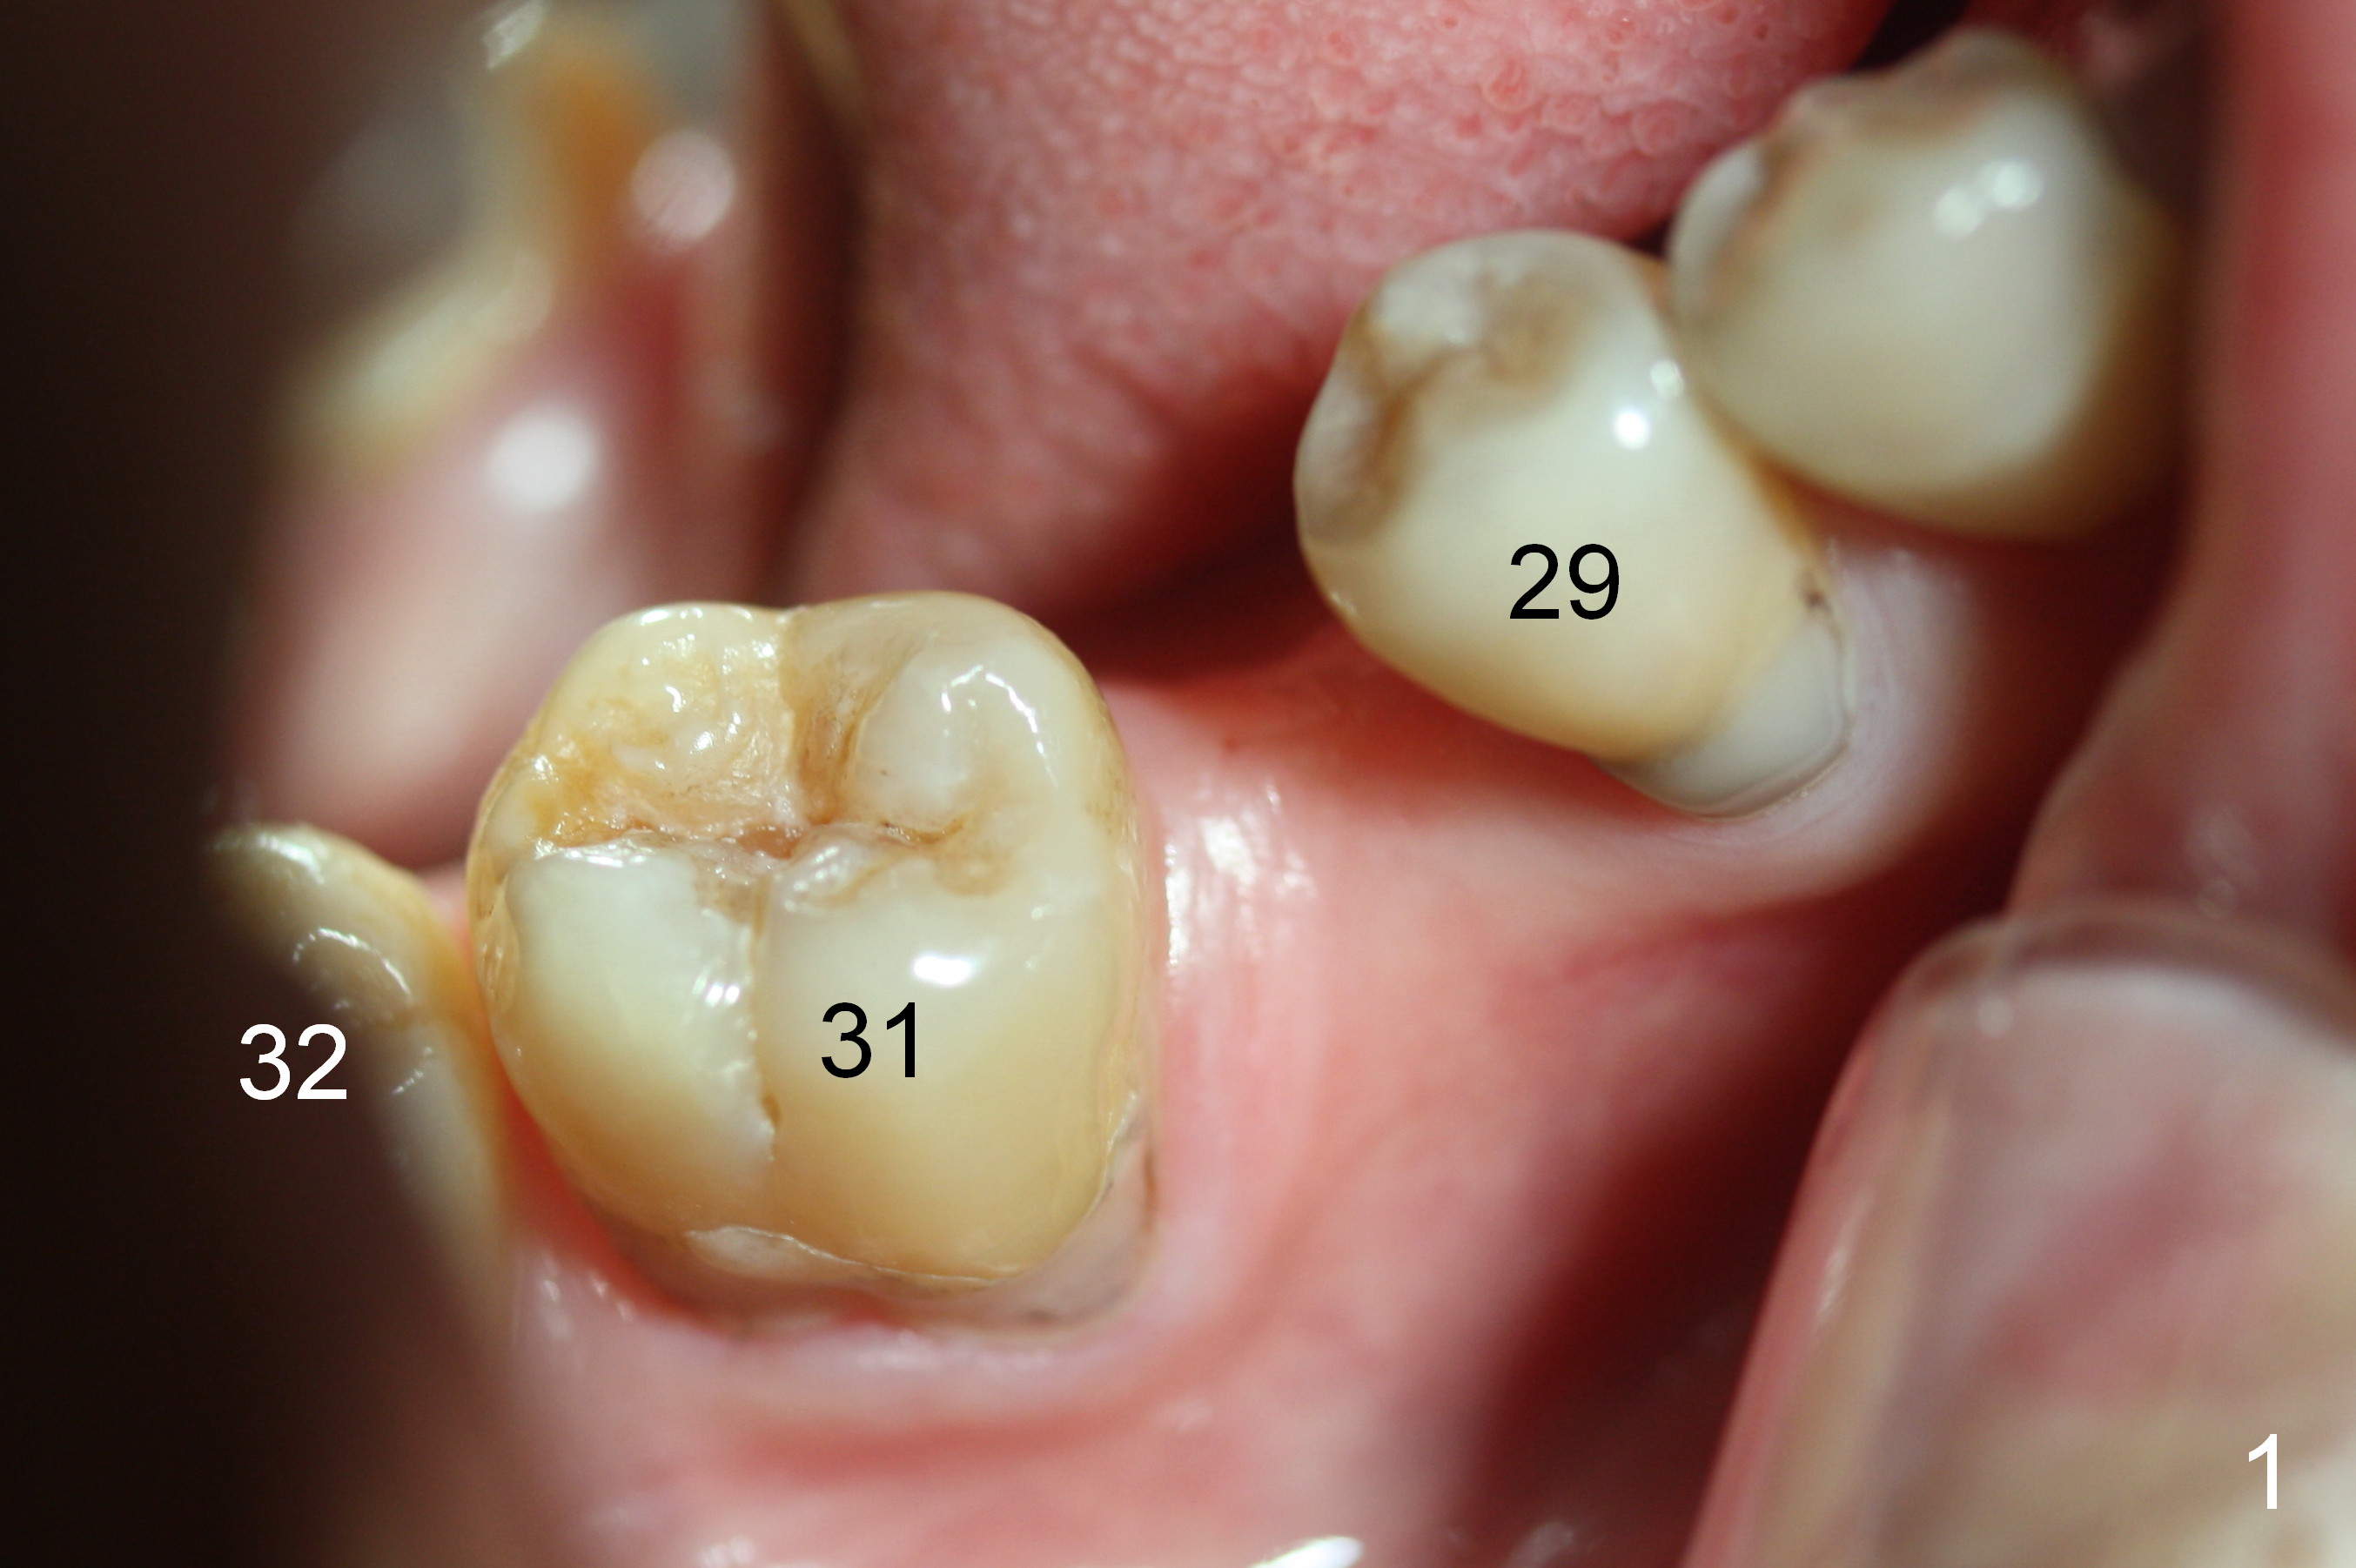

A 47-year-old lady has lost the lower right 1st molar for long time; with reduction of the buccolingual width (Fig.1) and mesiodistal width (Fig.2,3). With regional orthodontic appliance (Fig.4) for 3 months, the tooth #29 has started being distalized (Fig.5). One month and a half later, the tooth #26 starts to shift labially. Power chains and then closed coil spring are placed between #29 and 32. #29 distalization is slow (Fig.7) with closure of the diastema between #31 and 32 (Fig.8, as compared to Fig.1,3). Seven months post banding, a 10 mm miniimplant is placed distobuccal to the tooth #32 (Fig.6); the same 12-mm closed spring is stretched distal by ~ 6 mm (Fig.8 between arrowheads). Two months later, #29 is more distalized (Fig.9 tilted) with bone deposit mesially (*) and coronally (^). A .018' stainless steel wire is installed with an open coil spring placed between #28 and 29 (Fig.10 (^),11). Note #29 rotation (Fig.11). To solve the tilting, a power hook (Fig.12 black) will be clamped to a .016x.016 wire (red), while the closed spring is lowered and attached to the power hook (Fig.12 white). Take photos after removing the existing wire occlusally to show the alveolar width change. When the wire is placed, make sure that the distal wings of #29 bracket is fully engaged to reduce the tooth rotation. Make occlusal adjustment on #31 and 32 to reduce anterior open bite.